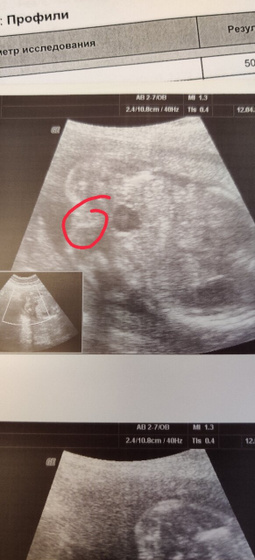

Сегодня нам сказали пол??? доченька

Наконец то разглядели пирожочек)) я рада, сын хотел брата конечно, но я хотела нежную девочку, ура) теперь можно покупать понемногу наряды)